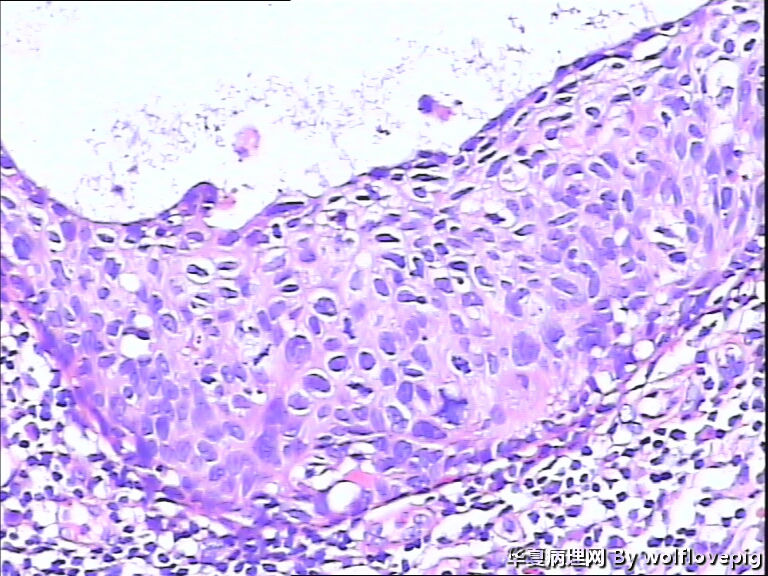

求助,宫颈!

37y

CIN3累腺

CINIII累及腺体